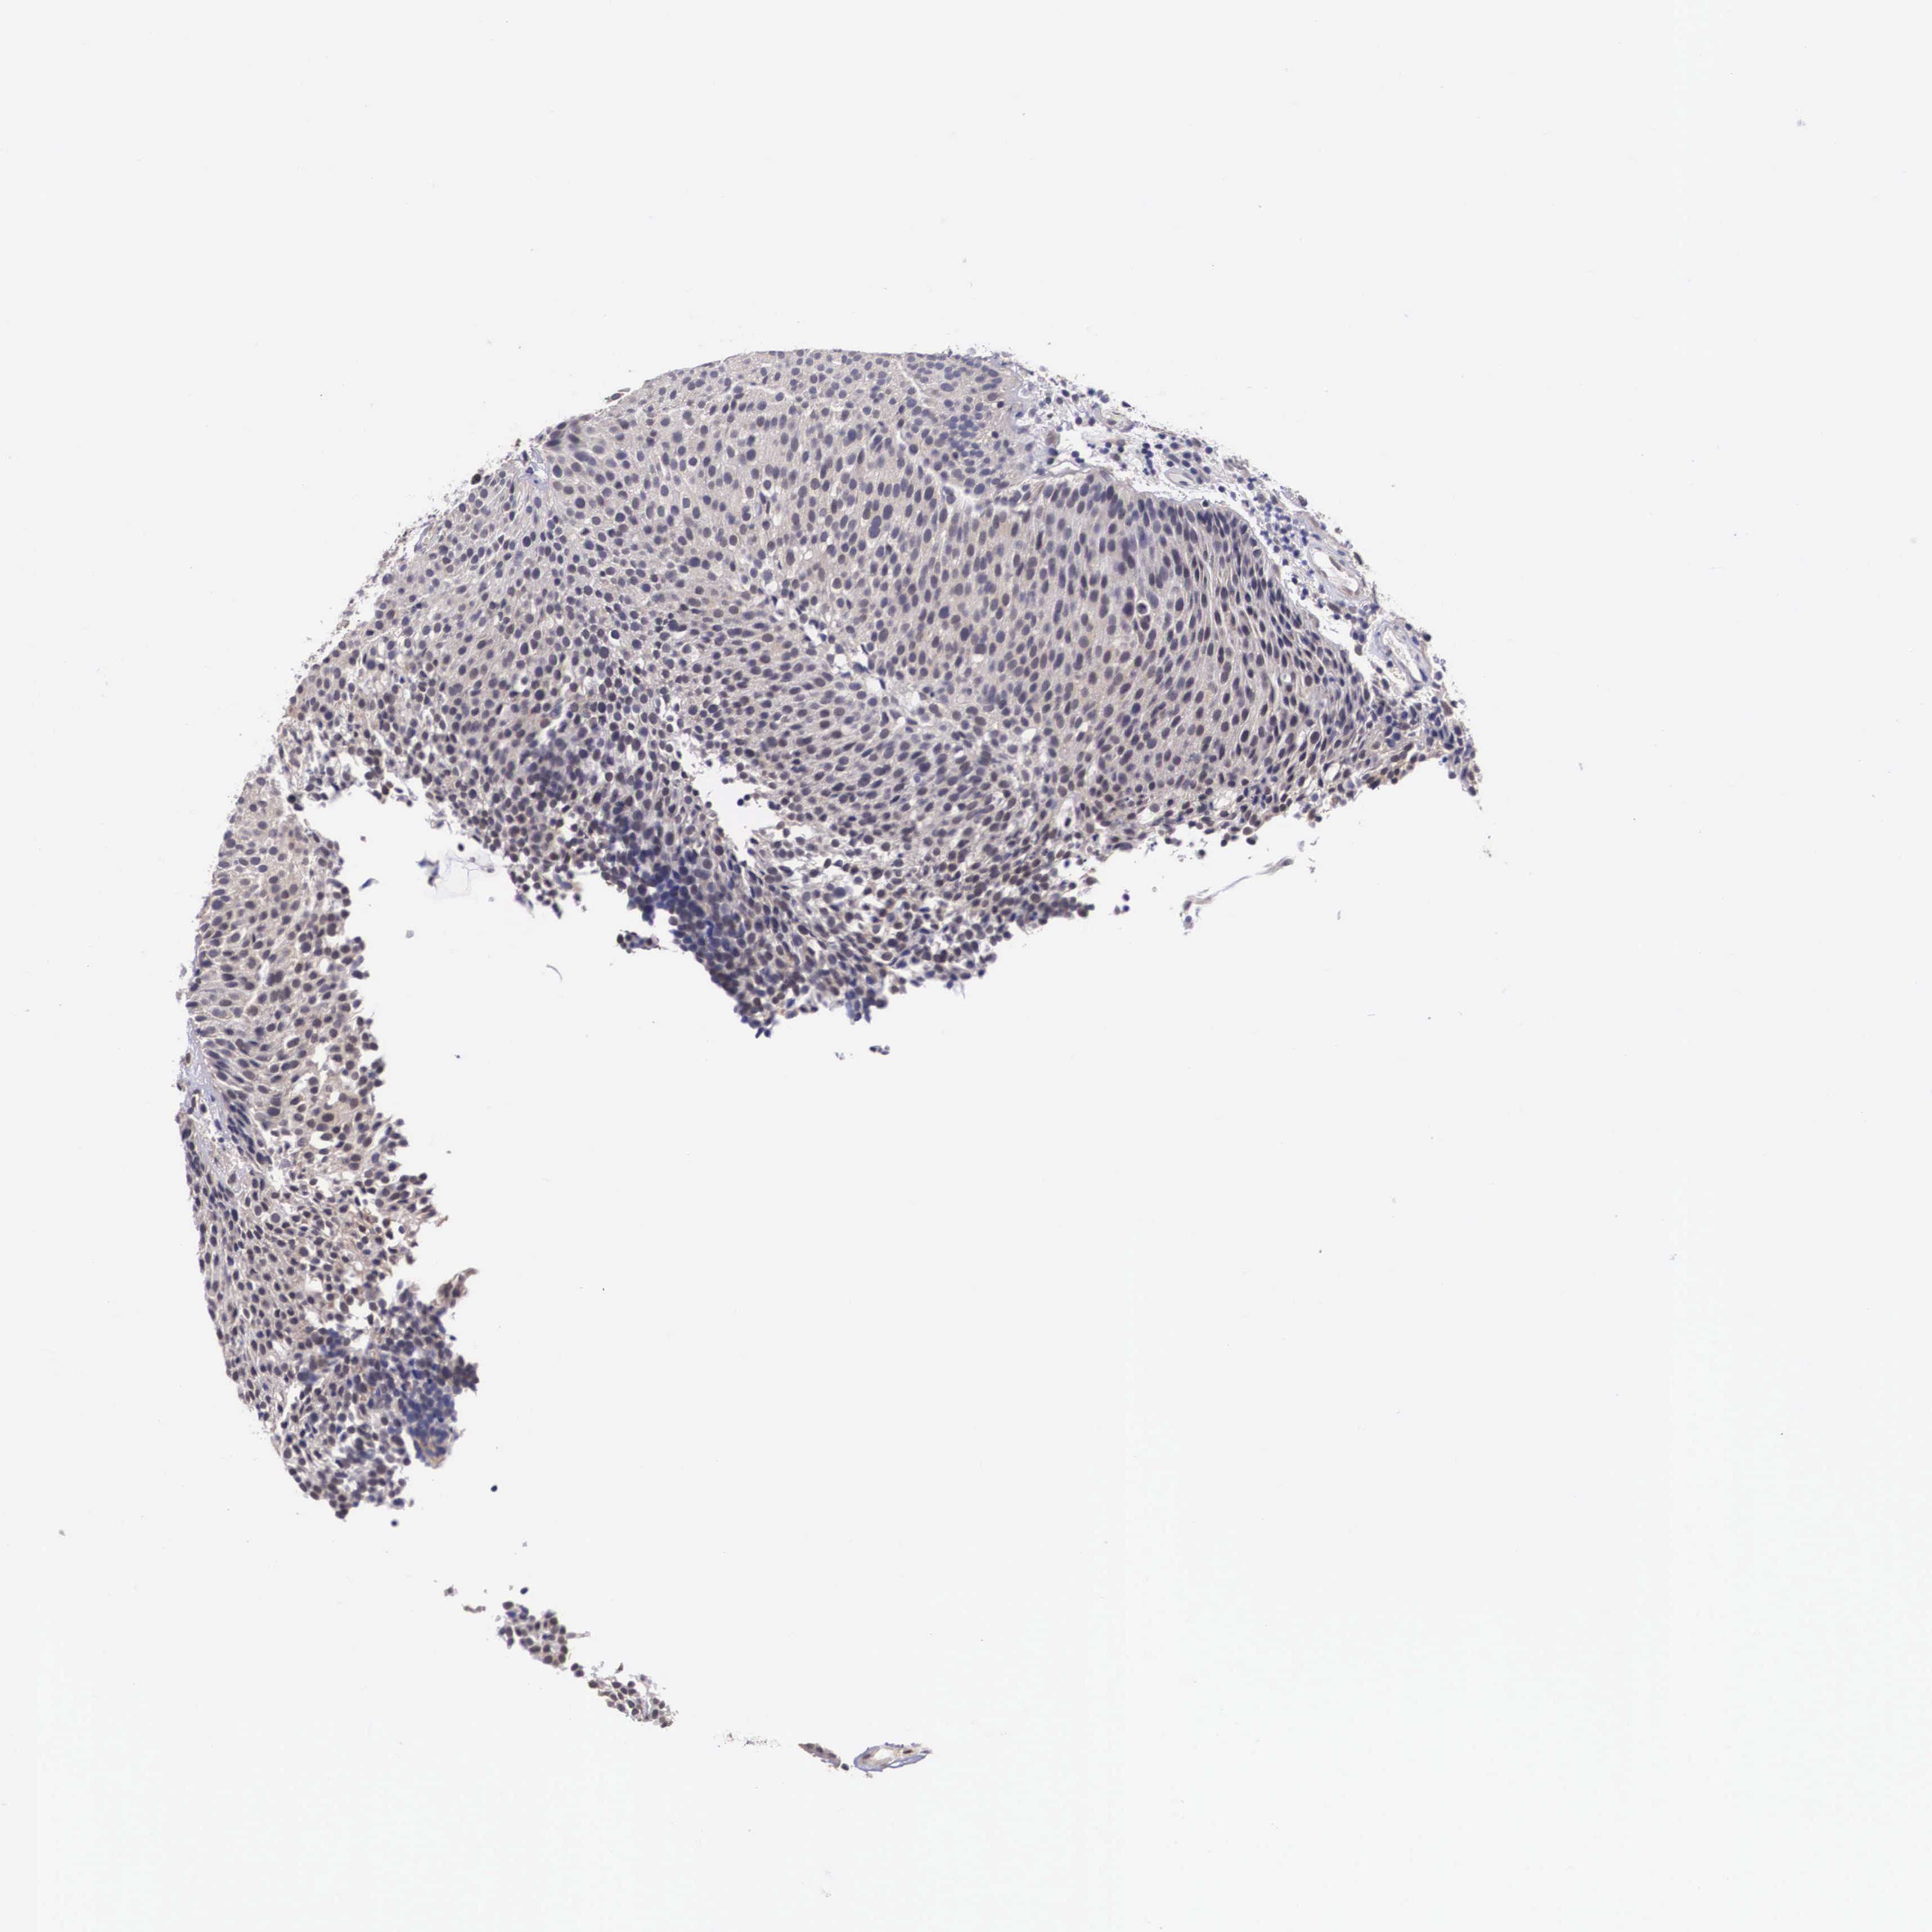

UROTHELIAL CANCER - Protein expressioni

A mouse-over function shows sample information and annotation data. Click on an image to view it in a full screen mode. Samples can be filtered based on level of antibody staining by selecting one or several of the following categories: high, medium, low and not detected. The assay and annotation is described here.

Note that samples used for immunohistochemistry by the Human Protein Atlas do not correspond to samples in the TCGA dataset.

Antibody stainingi

Antibody staining in the annotated cell types in the current human tissue is reported as not detected, low, medium, or high, based on conventional immunohistochemistry profiling in selected tissues. This score is based on the combination of the staining intensity and fraction of stained cells.

Each image is clickable and will lead to virtual microscopy that enables deeper exploration of all samples and also displays staining intensity scores, fraction scores and subcellular localization as well as patient and tissue information for each sample.

Antibody HPA000633

Staining

High

Medium

Low

Not detected

Intensity

Strong

Moderate

Weak

Negative

Quantity

>75%

75%-25%

<25%

None

Location

Nuclear

Cytoplasmic/membranous

Cytoplasmic/membranous,nuclear

Urothelial carcinoma, Low grade